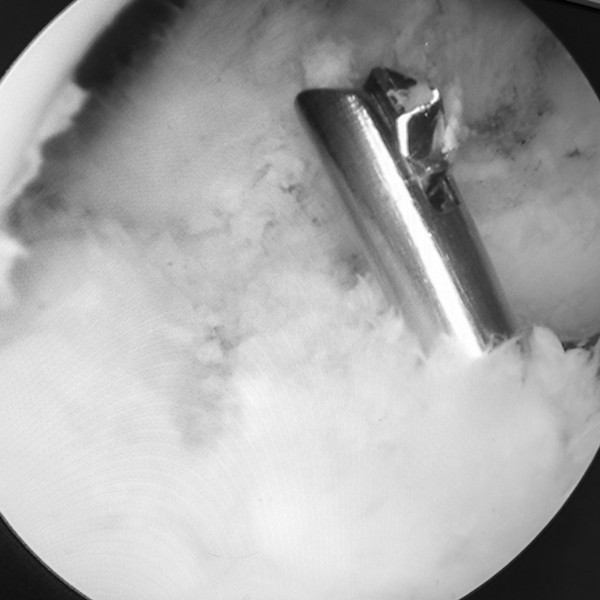

术中利用倒打钻完成套接骨隧道的制备